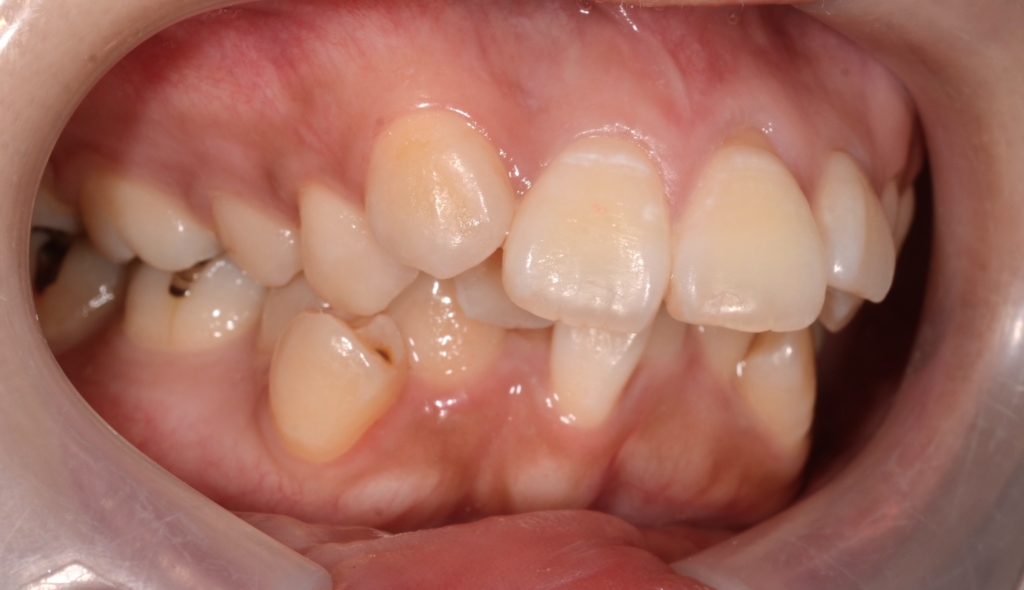

#1.歯と顎の不調和による叢生(重度)

#2.上顎前突

【治療方針】

1.先ず、奥歯を抜歯して、歯並びを整える

2.次いで、アンカースクリューを用いて、上顎の歯列を更に後方へ移動

という治療計画にて、矯正を進めることにしました。